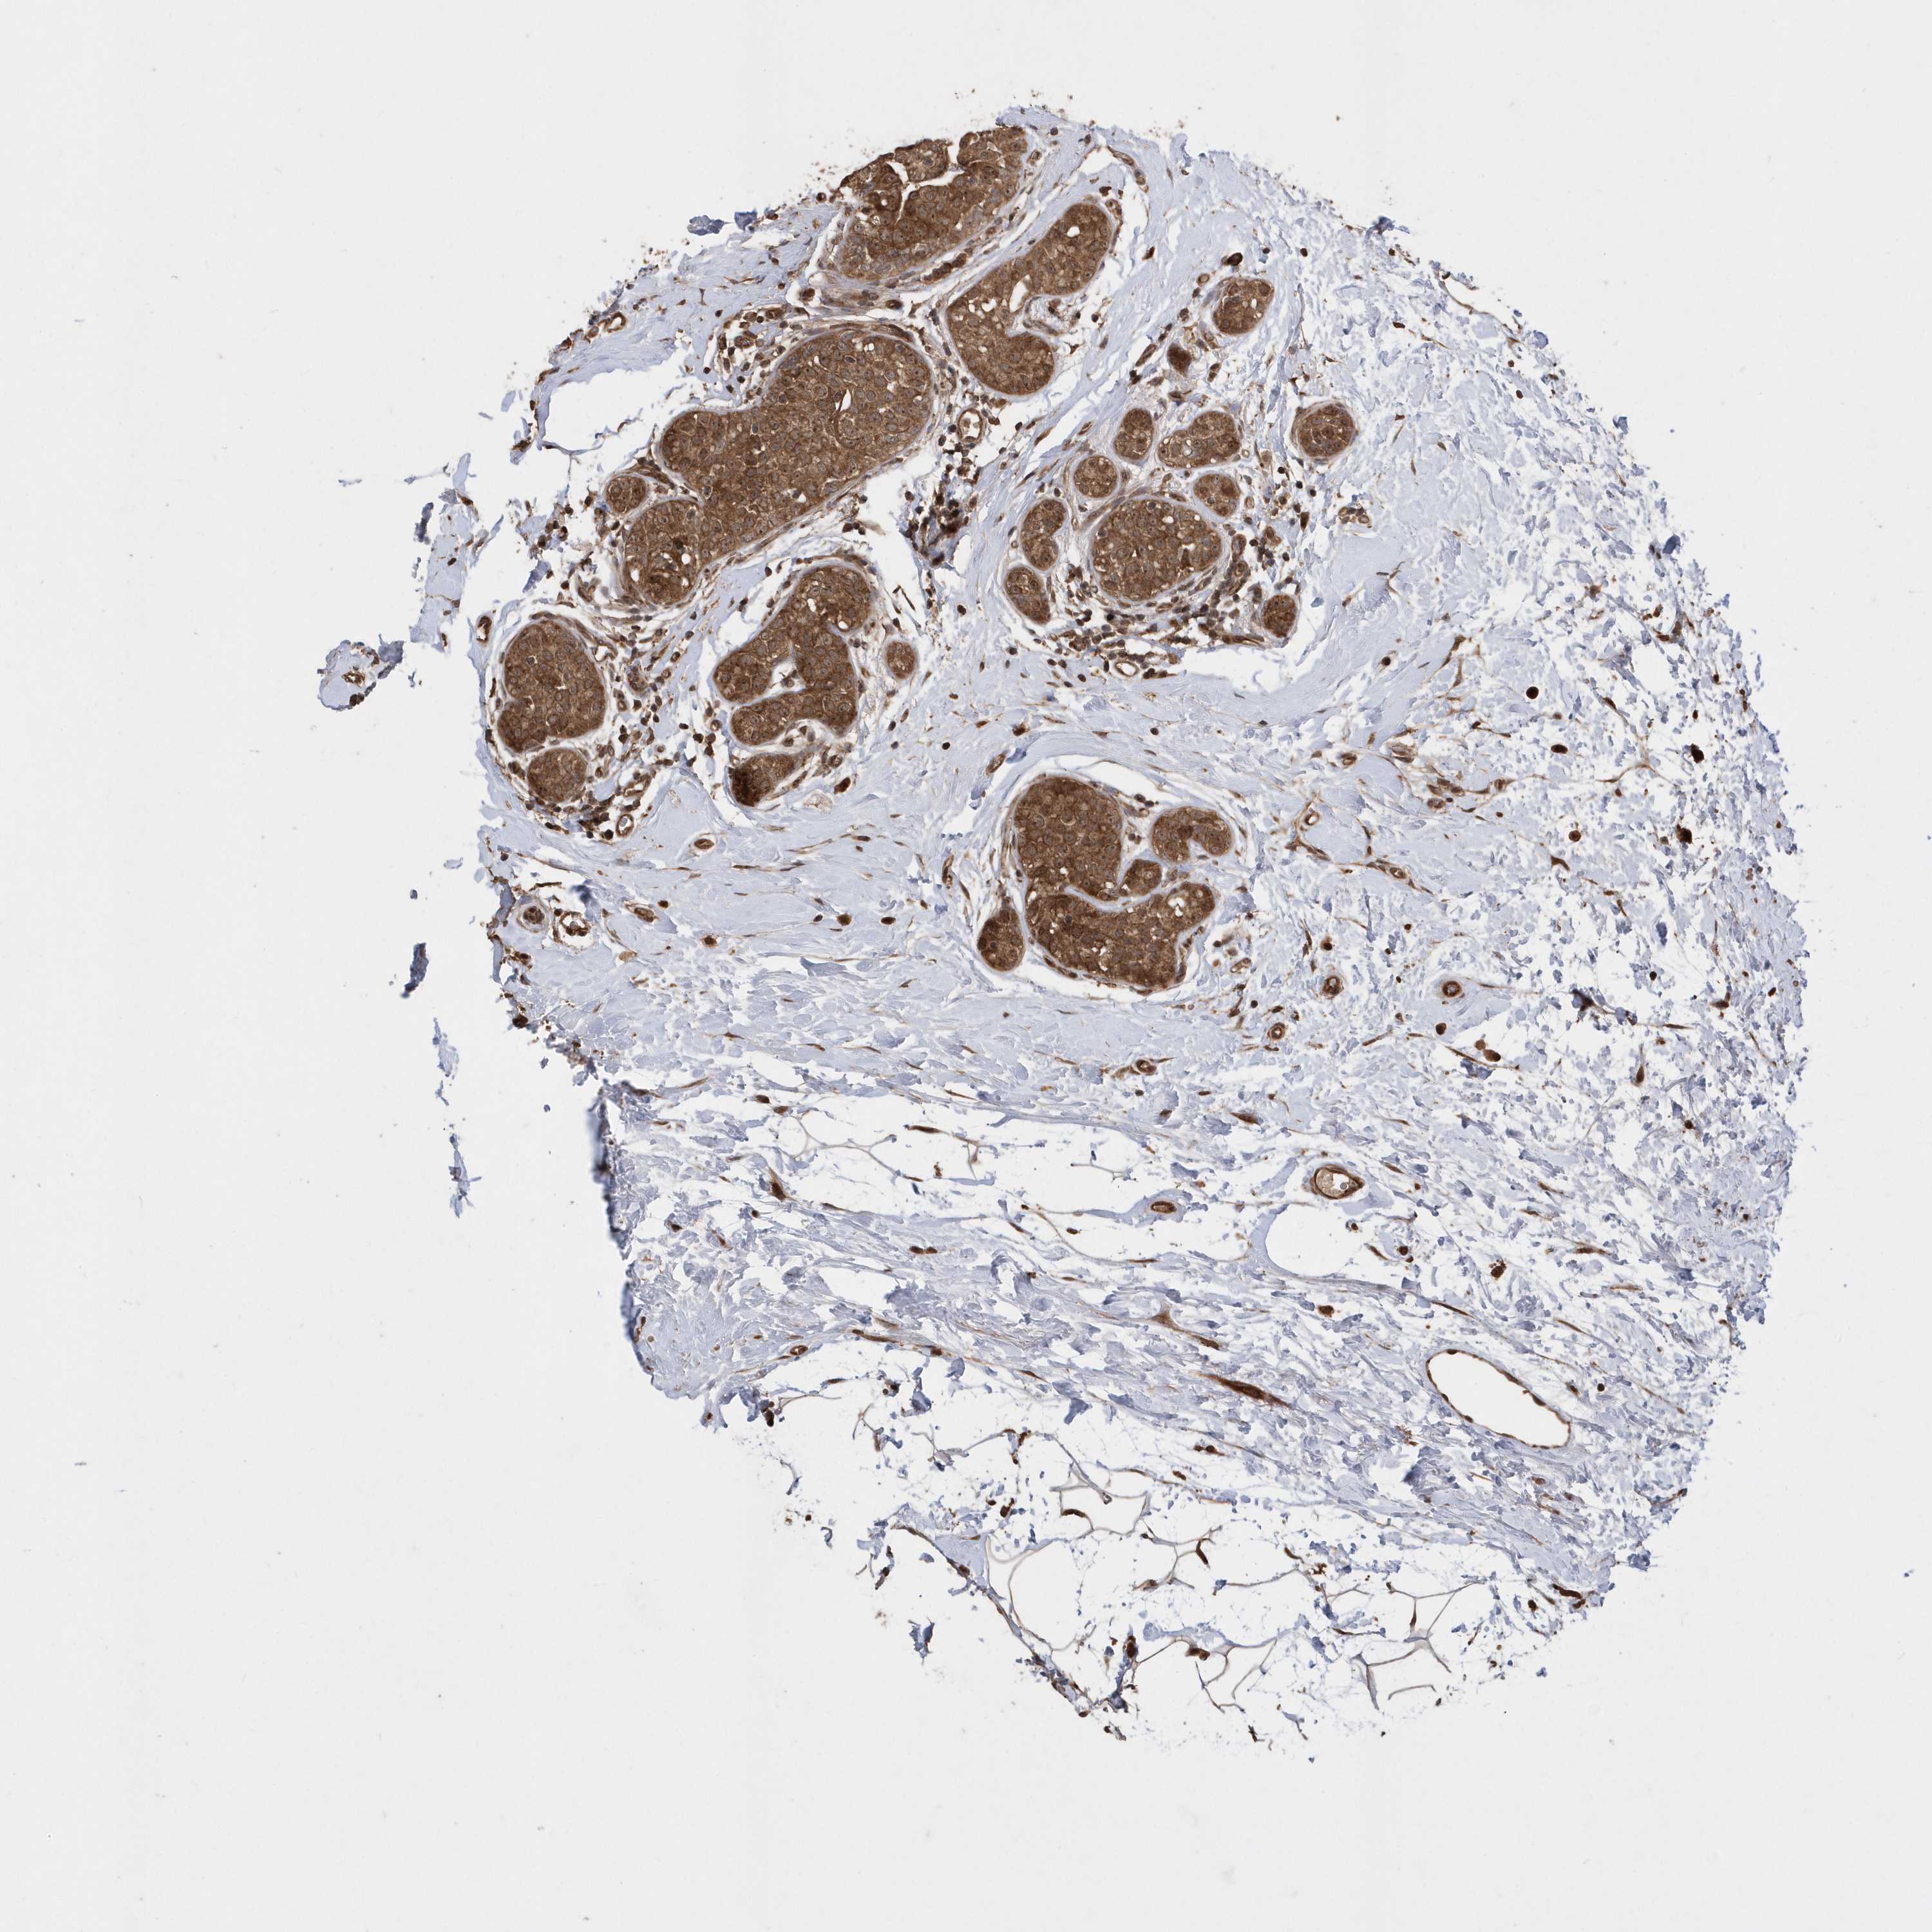

CANCER BREAST CANCER Show tissue menu

BRCA TCGA BRCA VALIDATION PROTEIN EXPRESSION